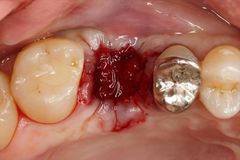

口腔外科処置

頬舌的に割れていた右上第一大臼歯を抜歯しました。2017.08.08